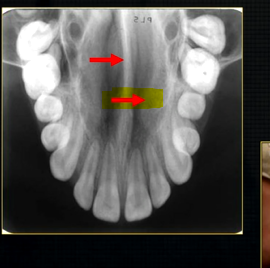

what does this anterior periapical graph show?

oval radiolucent area between the central incisors - is it Infront of the teeth (buccally?) or is it behind them? - you can’t tell radiographically

but its shape and position is compatible with the palatally positioned with the nasopalatine formaina

more posteriorly - radiopacities indicate the nasal septum and floor of the nose

dense, thin , white line in the middle of the image is the nasal septum

less dense opacity is caused by the

inferior nasal concha

radiolucency - nasal septum

lateral wall of the nose

maxillary air sinus

mid-palatal suture

this increased radiopacity is caused by the soft tissues at the tip of the nose - shadow - dense tissue